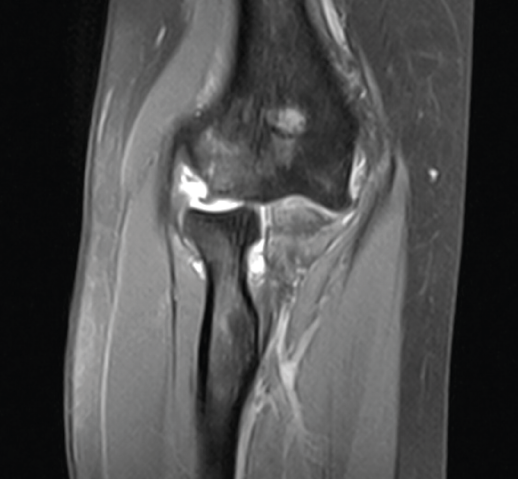

Conforme va recuperando el arco de movilidad, la paciente refiere sensación de inestabilidad, que ella lo refiere “como si se le saliera algo del sitio”. Con esta situación, es remitida a nuestras consultas, solicitándole una resonancia magnética (RM) de codo izquierdo.

En las imágenes de RM podemos ver los signos de arrancamiento de la inserción proximal de ligamento colateral lateral, importante cantidad de derrame articular y el edema óseo localizado en toda la parte medial del humero distal y del cúbito y el radio proximales (Figura 5).

Figura 5. Imagen coronal de resonancia magnética del codo izquierdo, realizada a las 3 semanas de la lesión. Observamos la avulsión proximal del ligamento colateral lateral, la subluxación de la cabeza radial y el edema óseo.